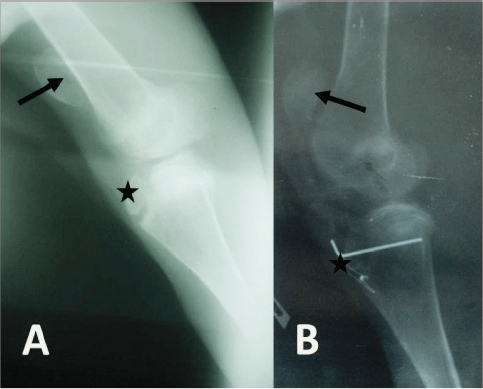

Radiographically, the stifle areas of the affected goats showed ventrocaudal PL in three cases (Figs. 2 and 3) and dorsal PL in the other two cases, for which surgical treatment was performed (Fig. 4A).

Fig. 4. (A) Mediolateral radiograph of the right stifle of a 10-month-old goat showing a dorsal PL (arrow) with no signs of trochlear ridge hypoplasia. There is also an avulsion fracture of the tibial tuberosity (star). (B) Mediolateral radiograph of the right stifle of the same goat immediately postsurgery showing that the patella (arrow) and the tibial tuberosity (star) are placed almost at their normal anatomical locations.